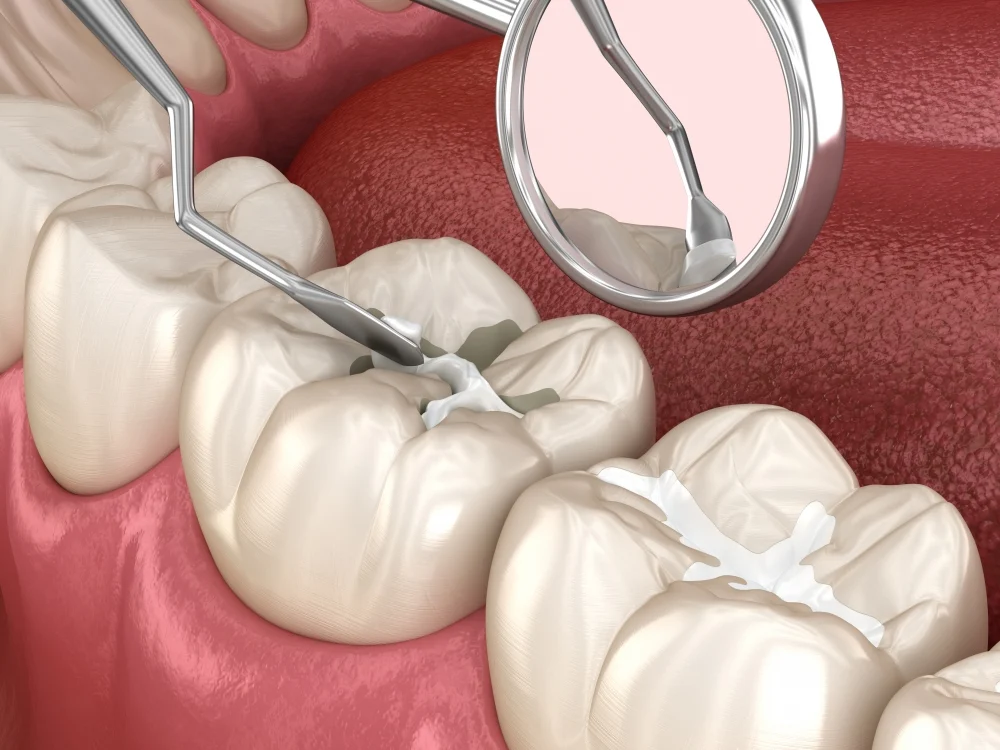

補牙材料:提供多種優質嘅材料,如美國3M樹脂等。呢啲材料具有色澤逼真、持久性佳、強度高嘅優點,能夠好地恢復牙齒嘅外形同功能。